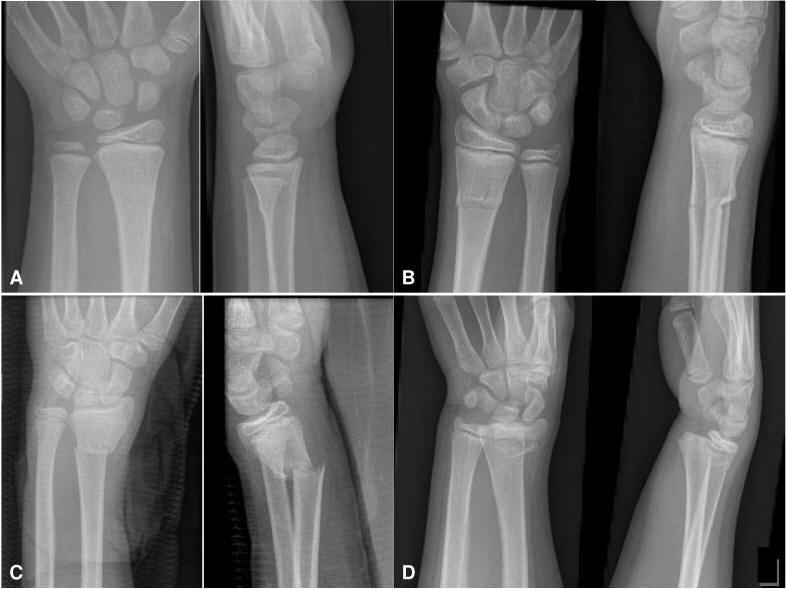

A Røntgen viser her Buckle fracture (En lille bule uden brud på corticalis)

B Greenstick fraktur med brud på corticalis på den ene side

C Komplet fraktur i distale radius.

D: Røntgen viser her epifysiolyse, her ofte Salter-Harris type II. Evt. kombineret med ulna Greenstick-fraktur/ ulnafraktur / processus styloideus ulnae fraktur.